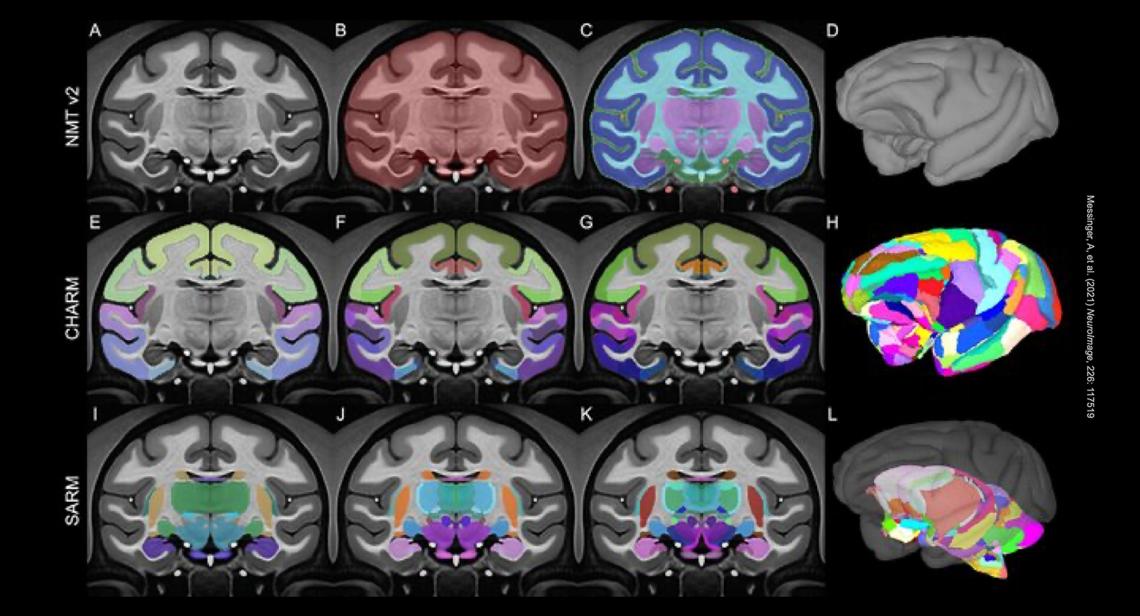

Messinger, A, et al. (2021) NeuroImage, 226: 117519